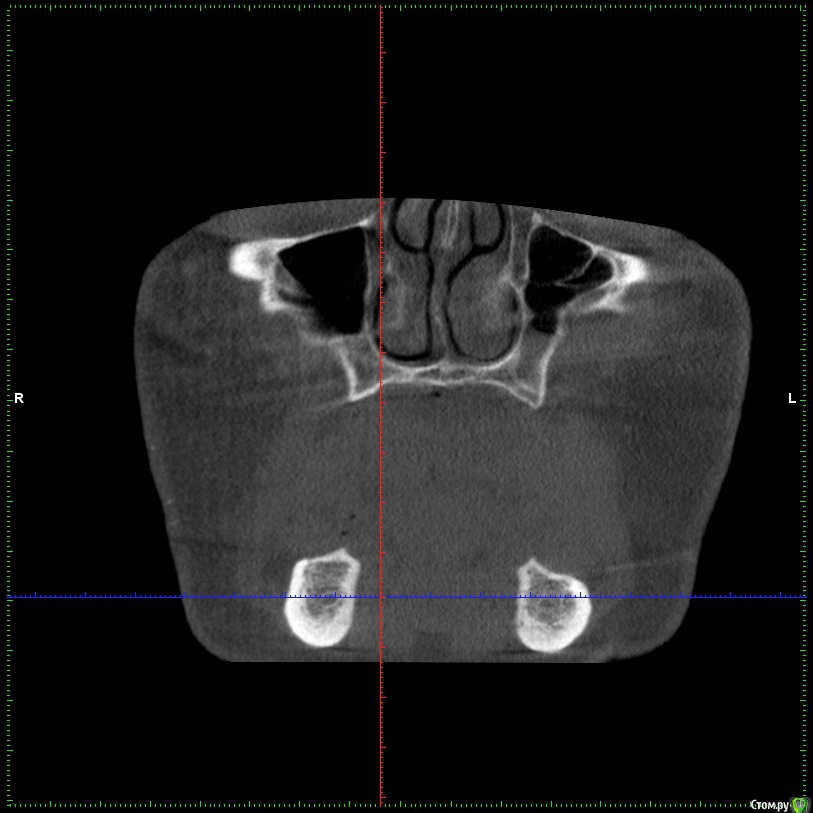

Aleksey_Mironov Опубликовано 11 января, 2018 Поделиться Опубликовано 11 января, 2018 здравствуйте коллеги!! вот такой сюрприз..хочу сделать синус лифтинг.. что за образование можеть быть? Ссылка на комментарий

Aleksey_Mironov Опубликовано 11 января, 2018 Автор Поделиться Опубликовано 11 января, 2018 здравствуйте коллеги!! вот такой сюрприз..хочу сделать синус лифтинг.. что за образование можеть быть? Ссылка на комментарий

Борис80 Опубликовано 11 января, 2018 Поделиться Опубликовано 11 января, 2018 Не совсем уверен, тк недостаточно срезов видно, но я бы сказал насморк или что-либо подобное(это по поводу тени) и , что значительно неприятнее, это костная перегородка на дне пазухи Ссылка на комментарий

колесников Опубликовано 11 января, 2018 Поделиться Опубликовано 11 января, 2018 (изменено) Может образоваться перфорация мембраны. Делайте 2 окна Изменено 11 января, 2018 пользователем колесников Ссылка на комментарий